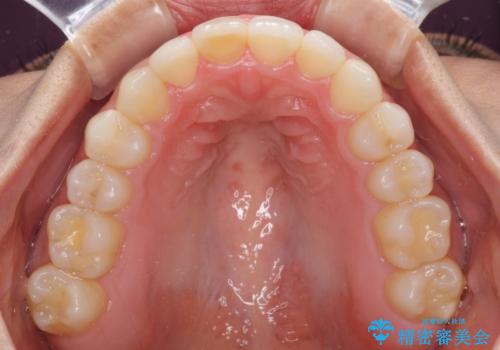

治療を長期化させたくないとのご要望があったので、左下の90度捻転した歯は、捻転した状態のゴールとしました。

反対咬合を改善したことで、歯ぎしりしたときの引っかかる感じがなくなり、奥歯への負担を大きく軽減することができました。